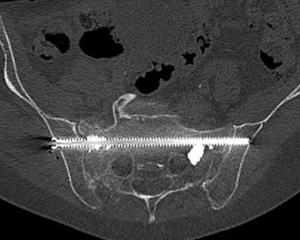

Les radiologues interventionnels utilisent des techniques d’imagerie (échographie, scanner, angiographie) pour réaliser des procédures mini-invasives à visée thérapeutique qui viennent en complément ou en alternative à la chirurgie.

Ces techniques permettent de traiter diverses pathologies sans nécessiter de grandes incisions, les patients n’ont donc pas de cicatrice au décours de l’intervention. Les procédures de radiologie interventionnelle sont souvent moins risquées et plus rapide que la chirurgie traditionnelle.